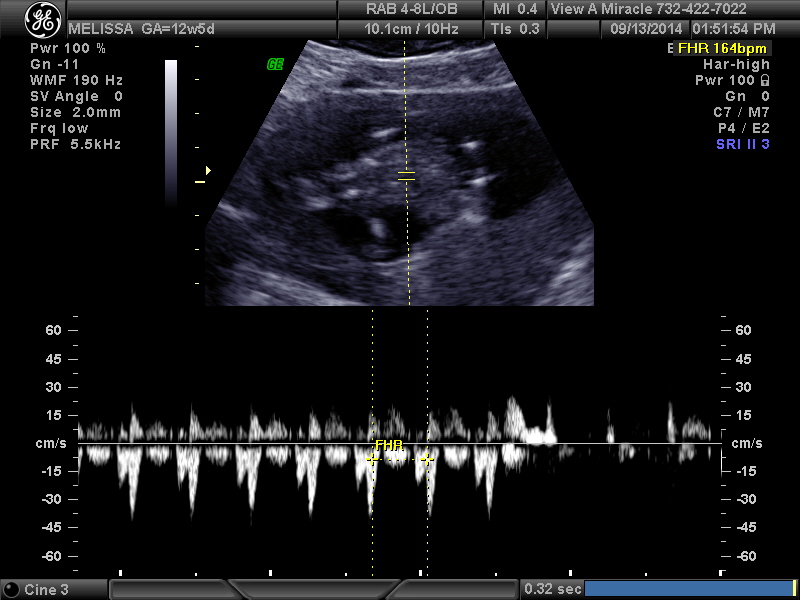

12 weeks 3 days. Tech told me girl and I'm over the moon but I think the potty shot looks like a boy... Opinions please!!!!

I'd really, really, really take that with a grain of salt. 12+3 is really too early to guess on anything but a nub. And even nubs at that stage are not really as accurate as you are looking for. I'd try to keep in mind that it still might be a boy. Not because I think the tech is necessarily wrong, but I think it's a tad irresponsible of a tech (even a trained one) to guess so definitively that early.

Hmmm. Honestly from these I'd say boy. It's still early though.